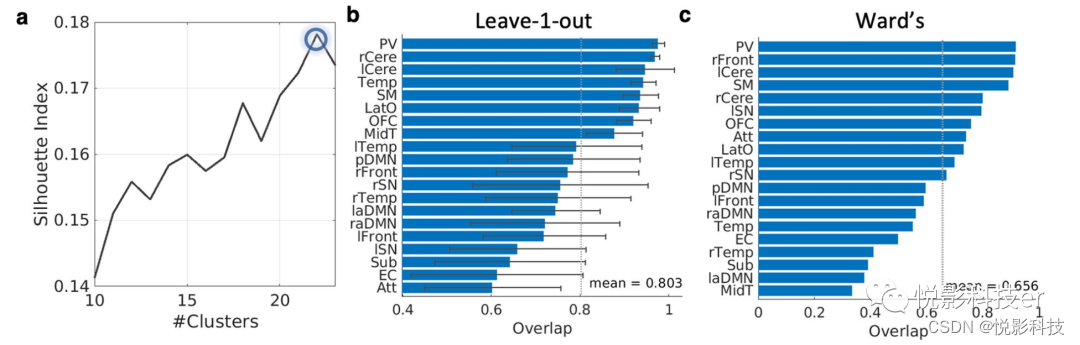

谱聚类算法从rs-fMRI数据中识别出22个功能网络。图5a展示了轮廓系数,表明轮廓系数在大脑被分为22个功能网络时达到最大值。目测舍弃2个主要位于脑白质和脑脊液的功能网络,得到最后20个功能网络。图4展示了大脑轴向图上的20个功能网络,图6提供了每个网络的三视图。20种功能网络的描述信息如表S2所示。

图5 模型选择和脑功能分区可复制性